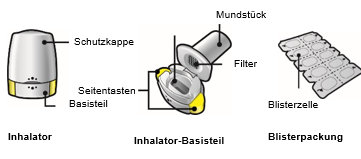

Diese Packung enthält den Inhalator und Kapseln in Blisterpackungen, die das Arzneimittel als Pulver zur Inhalation enthalten. Mit dem Inhalator können Sie das in einer Kapsel enthaltene Arzneimittel inhalieren. Verwenden Sie nur den in dieser Packung enthaltenen Inhalator.

·Diese Packung enthält einen Inhalator und Kapseln (in Blisterstreifen), die das Arzneimittel als Pulver zur Inhalation enthalten.

·Dieser Abschnitt der Packungsbeilage erklärt, wie Sie den Ultibro Breezhaler-Inhalator anwenden und pflegen müssen.

Wie ist der Inhalator anzuwenden?